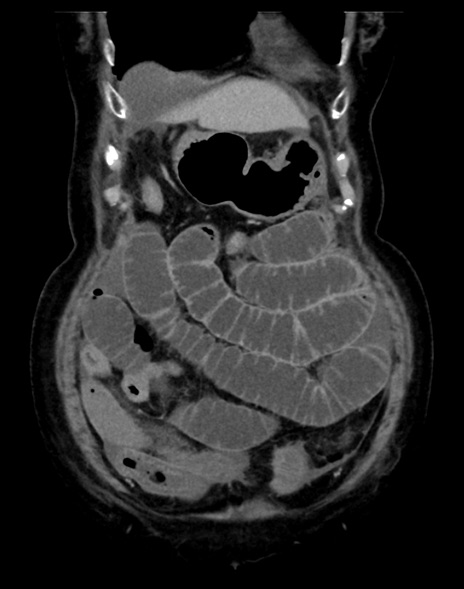

(横断像)1日半後